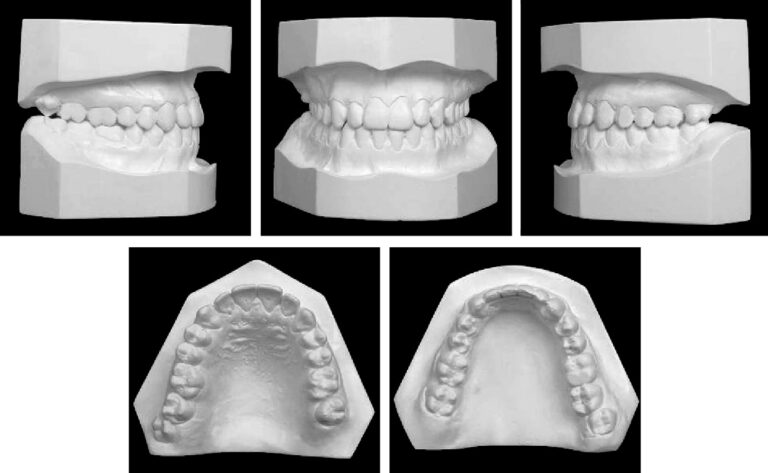

The patient was a man (age, 23 years 11 months) with a Class III subdivision left malocclusion with negative overjet and facial imbalance. His chief concerns were his anterior crossbite and lower lip protrusion. His parents had no Class III characteristics. The facial photographs showed a prognathic mandible and a Class III appearance (Fig 1). The patient could close his lips without mentalis strain, but he was self-conscious about the way his teeth occluded and the appearance of his teeth. The pretreatment intraoral photographs and dental casts show a Class III subdivision malocclusion with Class I on the right and Class III on the left (Figs 1 and 2). There was good alignment of the mandibular incisors, and all teeth were present including the third molars (Fig 3, A). Cephalometrically, he had maxillary retrusion, slight mandibular protrusion, and a balanced facial pattern, with the exception of excessive lower anterior face height. The maxillary incisors were bucally tipped and protruded, and the mandibular incisors were lingually tipped and retruded. He had an acute nasiolabial angle (Fig 3, B and C; Table).

Fig 2. Pretreatment dental casts.

Fig 3. Pretreatment panoramic and cephalometric radiographs and tracing.